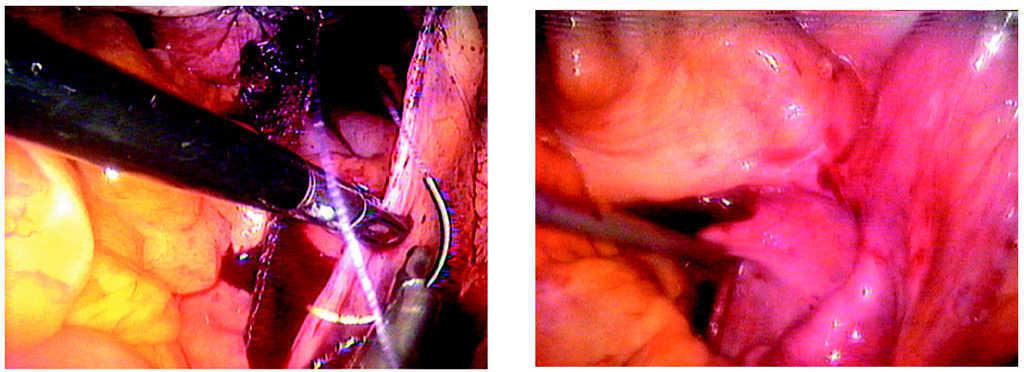

-- Paso cuarto. Colocación de 2 piezas rectangulares de malla de polipropileno (Gynemesh; Ethicon Inc. Somerville, NJ) en forma de Y sobre las caras anterior y posterior de la vagina (figs. 14-17).

Figuras 14 y 15. Fijación de la malla con puntos endoscópicos con sutura no reabsorbible sobre el músculo pubococcígeo.

Figuras 16 y 17. Fijación de la malla con puntos endoscópicos con sutura no reabsorbible sobre la fascia vaginal en su cara anterior y posterior.

-- Paso quinto. Fijación de la malla con puntos endoscópicos con sutura no reabsorbible sobre el promontorio del sacro (figs. 18 y 19).

Figuras 18 y 19.Detalle de la fijación de la malla al sacro.

-- Paso sexto. Peritonización con una sutura continua para ocultar la malla. Visión final (figs. 20 y 21).

Figuras 20 y 21.Detalle de la peritonización de la malla.